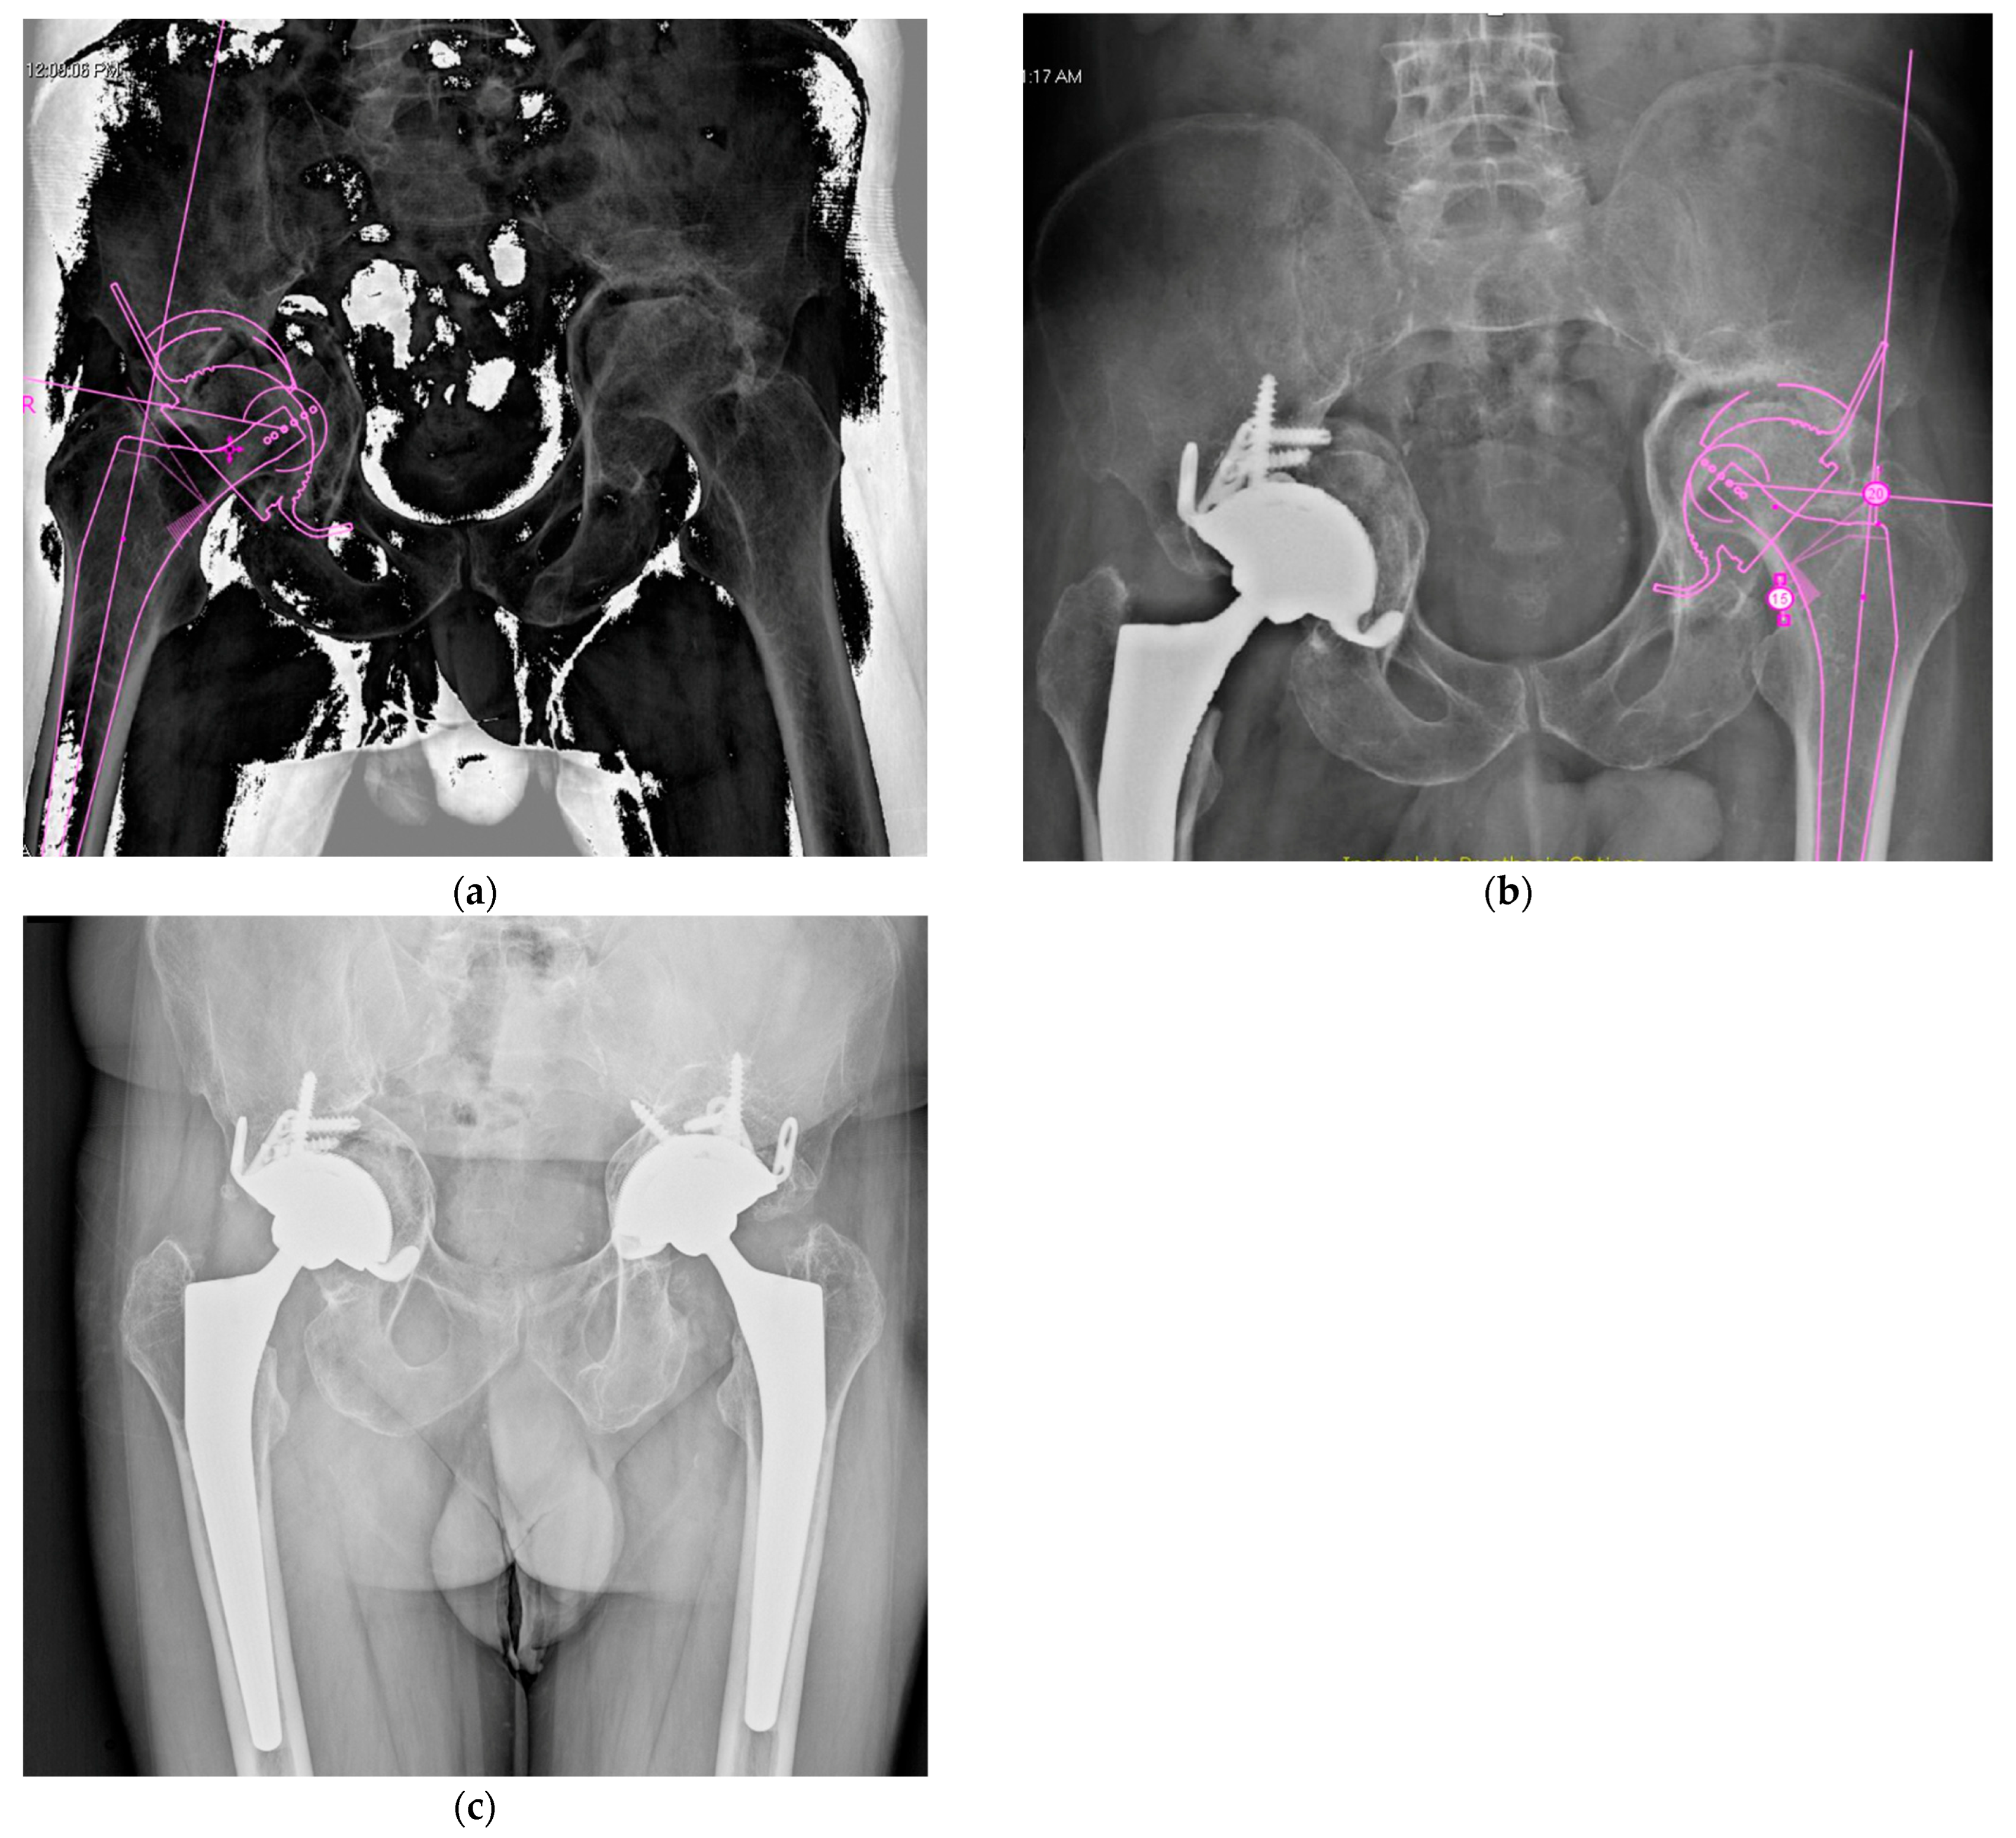

4.2. Late THA, Failure of Previously Operated Acetabular Fractures

4.3. Acute THA in Acetabular Fractures